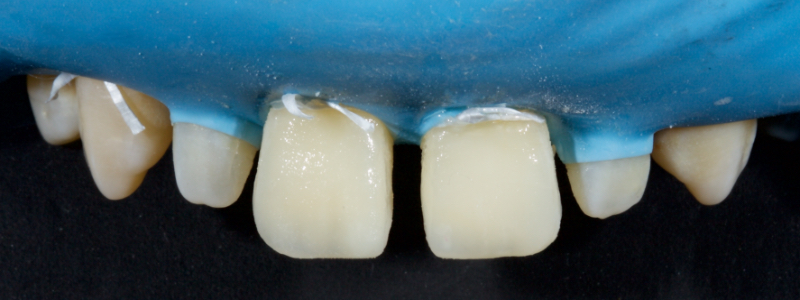

The chromatic enamels are built to full contour in the gingival and mid thirds but are under contoured in the incisal third (Figs. 18 and 19).

The next phase in the build-up is the application of a blue-grey resin mass in between the mamelon effects to create opalescence (Fig. 20). This should be sparing and confined to the incisal 2-3.0 mm. This layer should also be under contoured.

The final layering phase involves applying an achromatic enamel to the incisal third on the facial surface. This is adapted and smoothed with a flat plastic and a #3 brush/modeling resin (Figs. 21 and 22). The restoration is then polished.